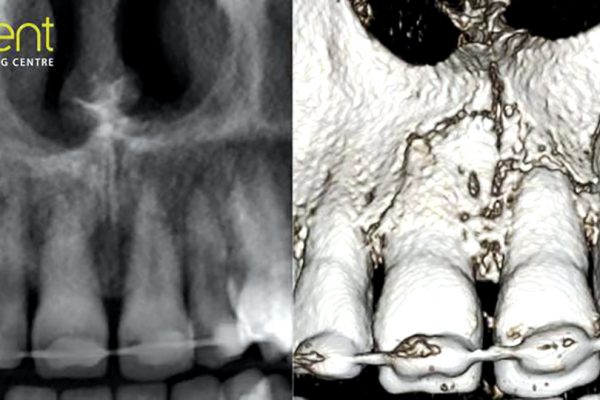

CBCT assessment of dental trauma

CT Dent presents a case where 3D imaging was used to identify the extent of hidden incisal trauma. This dentoalveolar…

Endodontics

Case of the month – periapical lesions

CBCT scanner: instrumentarium OP300 CBCT imaging protocol: 60x60x80mm, 0.2 voxel Effective dose: 0.04 mSv Clinical information: implants planned in upper aesthetic zone. Findings: paranasal sinuses…

Endodontics

CT Dent case of the month

Alex Woodham introduces this case from CT Dent. CBCT scanner: Instrumentarium OP300 CBCT imaging protocol: 60x60x80mm, 0.2 voxel Effective dose:…

Implant dentistry

Case of the month

CT Dent introduces a case where its scanners were used to diagnose the patient. Images provided Cone beam CT images in…

Dentistry